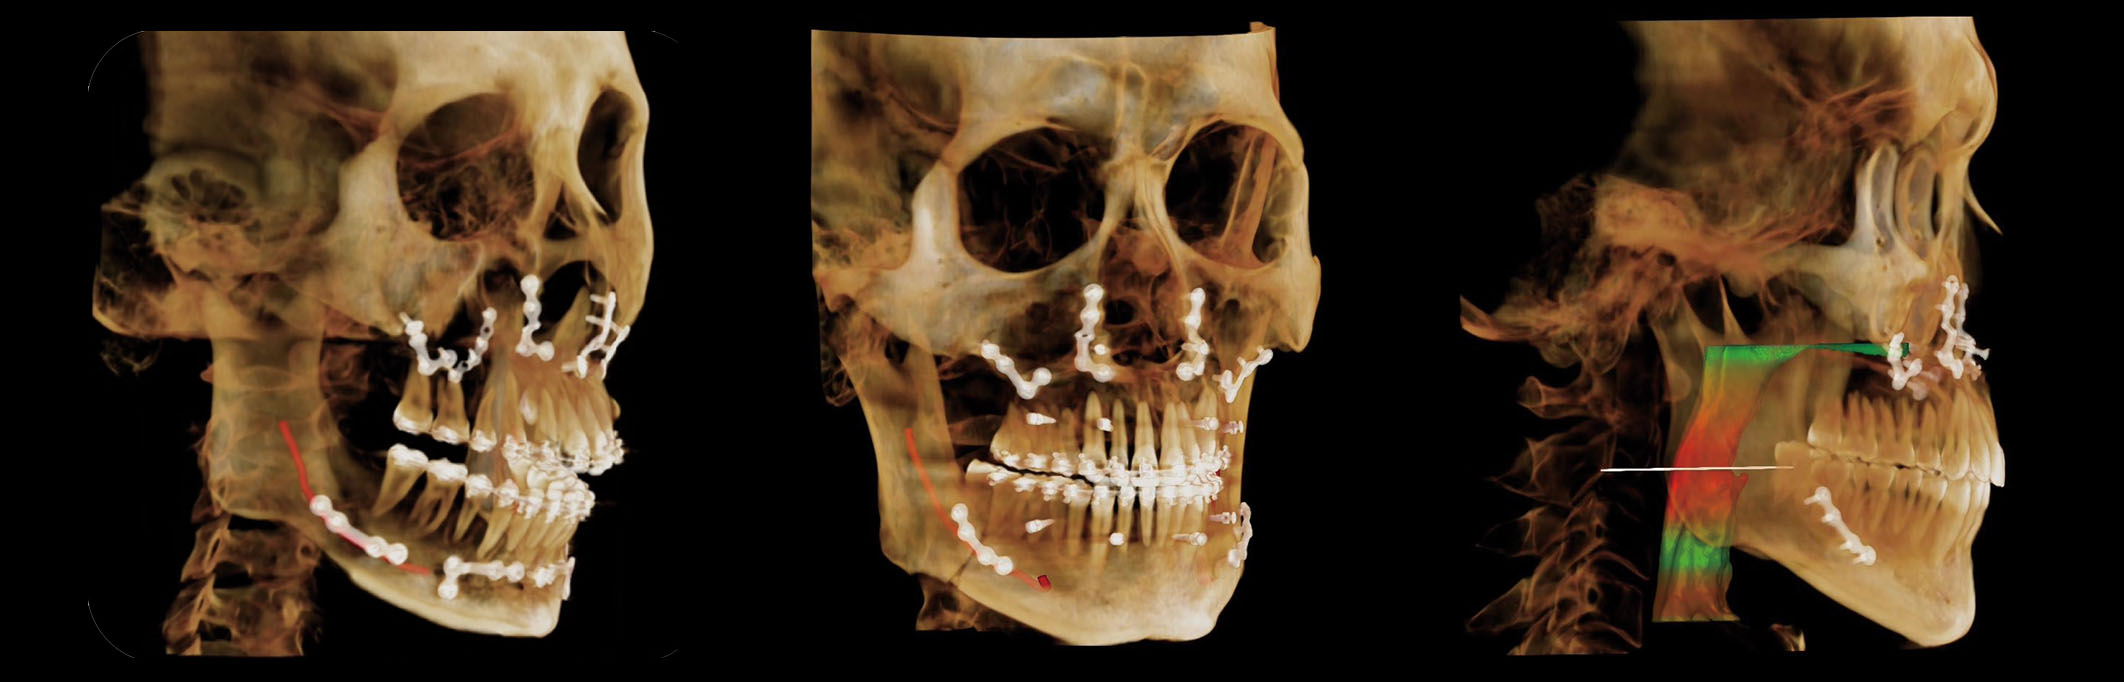

Tratamiento y Cirugía de Implantes Impulsados por IA

Herramienta de Planificación de Implantes por IA

La herramienta de planificación impulsada por IA detecta automáticamente los dientes y el nervio alveolar inferior, proporcionando alertas de seguridad en tiempo real. Soporta medición automática, simulación de implantes y optimización de trayectoria, lo que permite una planificación de tratamiento rápida y precisa.

Diseño de Guía Quirúrgica por IA

El módulo de guía quirúrgica de IA diseña automáticamente guías en un plazo de tres minutos. Los clínicos simplemente revisan y exportan los datos, con archivos STL e informes generados al instante, asegurando eficiencia y enfoque durante la cirugía.

Tratamiento y Análisis de Ortodoncia Impulsados por IA

Análisis de Vías Aéreas

La IA identifica y mide automáticamente el volumen de las vías aéreas y las áreas de sección transversal, generando un modelo visual 3D. Permite una evaluación rápida de las condiciones de las vías aéreas para el tratamiento de ortodoncia y para el diagnóstico de pacientes con ronquidos o SAHOS.

Análisis de ATM

El módulo de IA detecta y etiqueta automáticamente las estructuras clave de la ATM, analizando el espacio articular y la simetría. Asiste a los clínicos en la identificación de anomalías funcionales y en la optimización de ajustes de ortodoncia u oclusales.

Comparación Antes y Después

Rubik X1 alinea y compara automáticamente imágenes previas y posteriores al tratamiento, visualizando cambios dentales, esqueléticos y de tejido blando. Mejora la evaluación clínica y fortalece la comunicación con los pacientes.